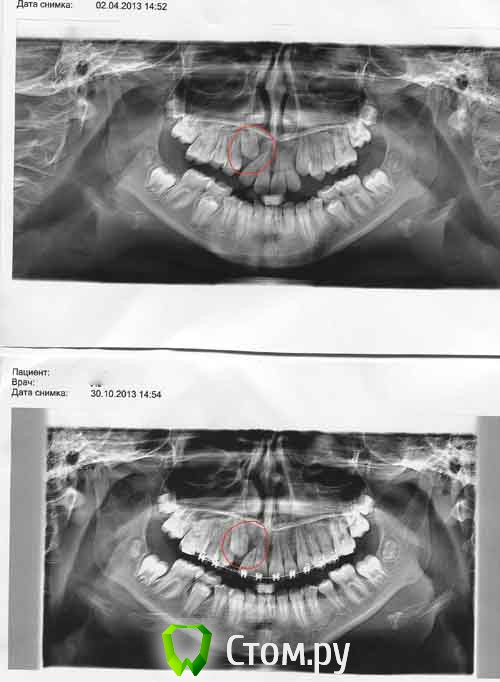

Ayrat_zub Опубликовано 29 ноября, 2013 Поделиться Опубликовано 29 ноября, 2013 по ОПТГ диагноз не ставится)) http://forum.stom.ru/topic/4655-patcientam/если "на глаз"- то дистопия клыка... Ссылка на комментарий

ИринаД Опубликовано 20 января, 2014 Автор Поделиться Опубликовано 20 января, 2014 (изменено) Прошу поставить диагноз девочке 12 лет. Снимок до установки брекетов апрель 12г. Помимо дистопии клыка на снимке киста, интересно было узнать видна она на раннем этапе на первом снимке. На втором снимке уже поздно, что либо предпринимать по лечению . Кисту удалили зуб (резец потеряли) Изменено 20 января, 2014 пользователем ИринаД 1 Ссылка на комментарий